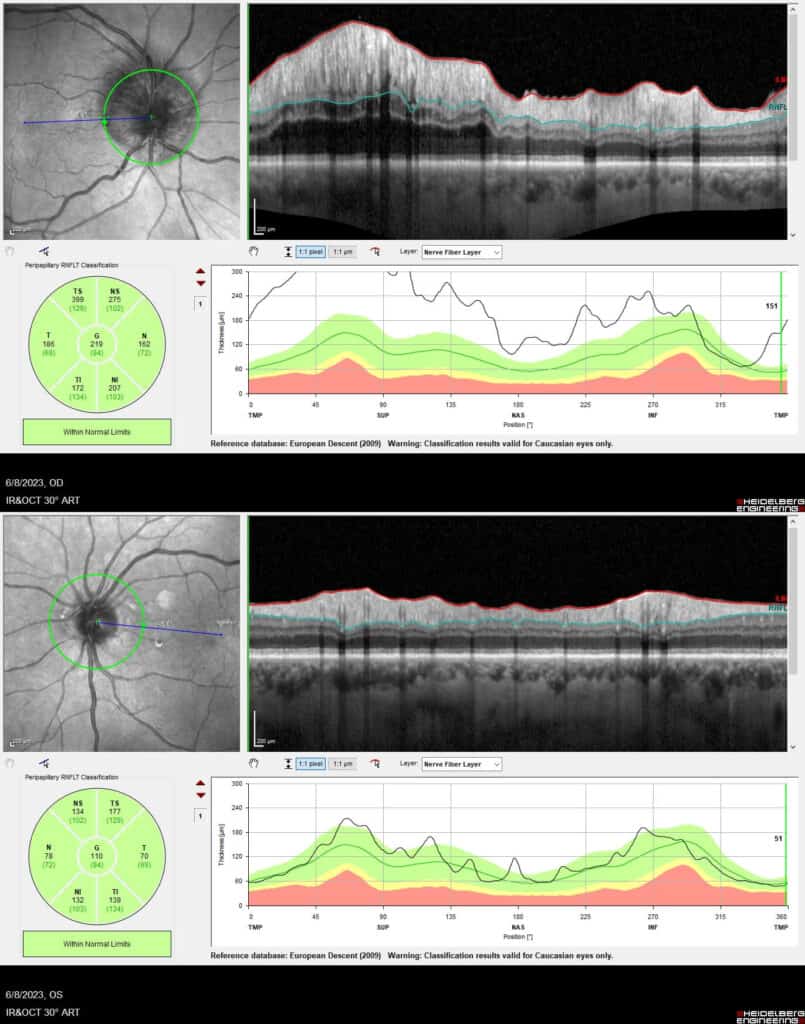

Upon testing, he maintained 20/20 acuity in each eye and normal ocular motilities. Newly noted findings were inferior constriction on confrontation fields in the right eye only and a 1+ right afferent pupillary defect. The intraocular pressure was measured to be 16 mmHg OD and 18 mmHg OS by applanation tonometry. The right optic nerve was edematous with blurred disc margins, lack of a cup and a mild hyperemic appearance (Figure 1). This was confirmed by OCT imaging demonstrating nerve fiber layer thickening, more so superiorly (Figure 2). The optic nerve of the left eye was a small disc with a 0.25 cup-to-disc ratio and distinct margins. The remainder of his dilated ocular health was unremarkable. Visual field testing revealed an inferior altitudinal defect in the right eye and a full visual field in the left eye (Figure 3).

Figure 2. (Top) OCT imaging on initial presentation show diffusely thickened nerve fiber layer, most significantly superior OD; (Bottom) no edema OS.

At his three-month follow-up he presented without visual complaints. His acuity remained 20/20 in each eye with inferior restriction on confrontation fields in the right eye and full in the left eye. There was a trace right afferent pupillary defect and improving optic nerve edema (Figure 4). However, the left optic nerve was now markedly edematous superiorly, with peripapillary hemorrhage and a small peripapillary cotton wool spot located superonasally (Figure 4). OCT imaging confirmed reduction in nerve fiber layer thickness OD and increased thickness OS compared to the prior images (Figure 5). Unfortunately, formal visual field testing was unreliable in the left eye with 56% false positive errors and 32% false negative errors.

Figure 5. (Top) OCT imaging at three month follow-up show reduction in nerve fiber thickness especially superiorly OD. (Bottom) thickening of the superior nerve fiber layer OS.